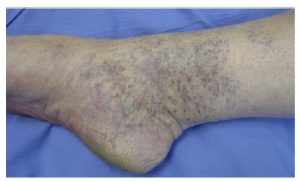

6. Venous Insufficiency and Bluish Feet

Veins return blood to the heart against gravity. When vein valves fail (“leaky veins”), blood pools in the feet.

Typical signs:

Purple or blue feet when standing

Improvement with elevation

Reticular (bluish) veins

Ankle swelling

Example – Venous Insufficiency:

Chronic venous insufficiency is very common and often underdiagnosed.